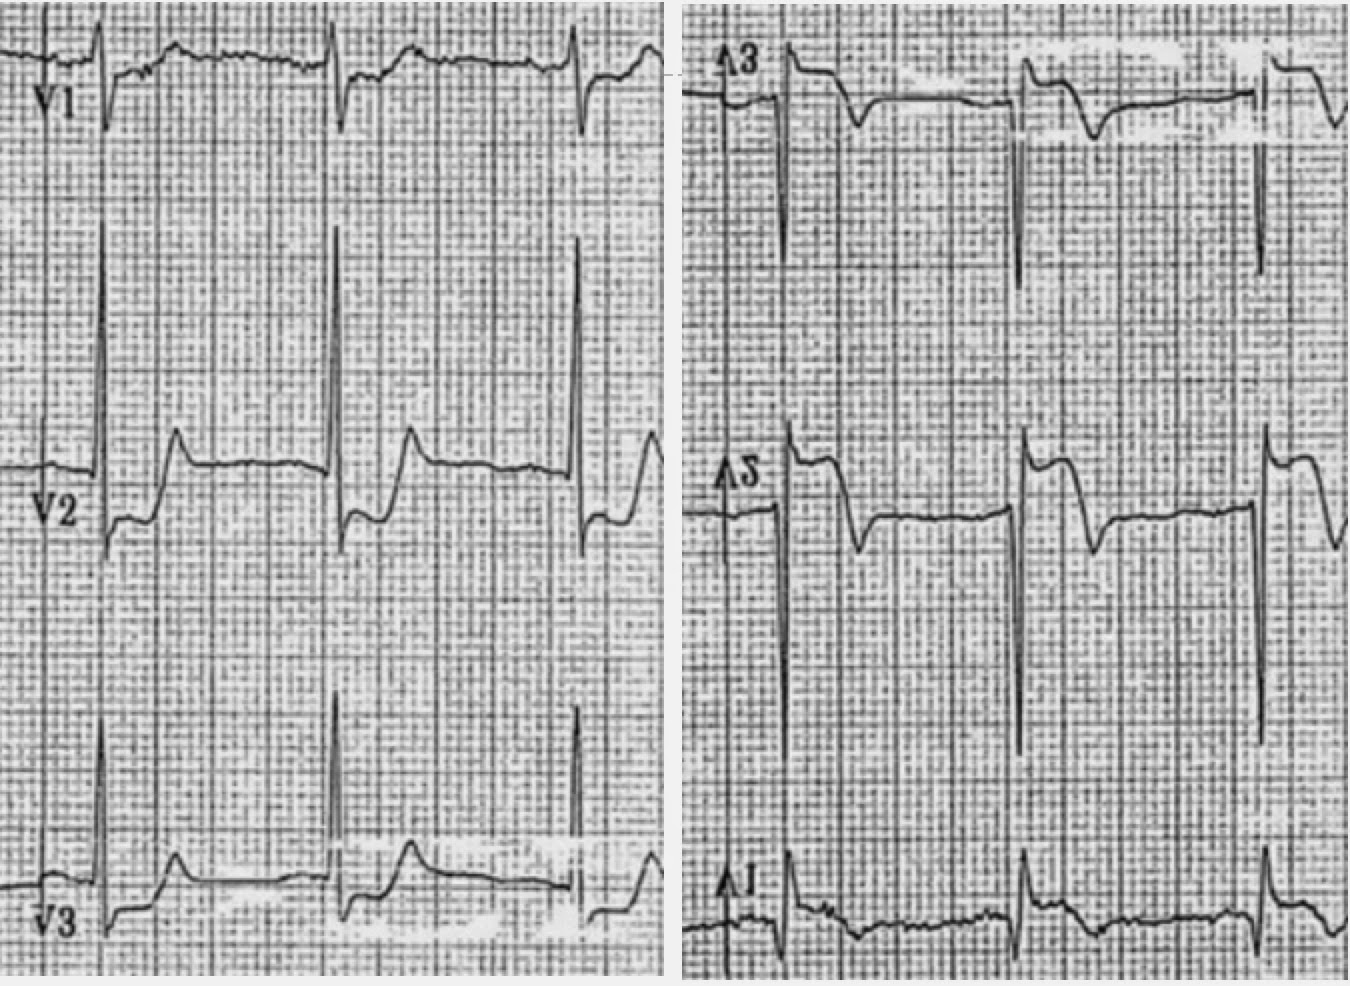

Mirrorimage ECG. ECG taken with right and left limb leads reversed and Mirror Image Ecg The progressive development of pathological r waves in posterior infarction (the “q wave equivalent”) mirrors the development. Today's ecg media pearl #60 (8:30 minutes audio) — reviews use of the mirror test to facilitate recognition of: Increased r wave amplitude and duration. Mirror images can be obtained consistently from all locations, supporting the dipole representation of cardiac electrical activity. The. Mirror Image Ecg.

(A) Leftsided ECG in a patient with mirrorimage dextrocardia and Mirror Image Ecg Increased r wave amplitude and duration. Today's ecg media pearl #60 (8:30 minutes audio) — reviews use of the mirror test to facilitate recognition of: The progressive development of pathological r waves in posterior infarction (the “q wave equivalent”) mirrors the development. Mirror images can be obtained consistently from all locations, supporting the dipole representation of cardiac electrical activity. The. Mirror Image Ecg.

(A) Placement of right precordial leads in a mirror arrangement to the Mirror Image Ecg The progressive development of pathological r waves in posterior infarction (the “q wave equivalent”) mirrors the development. Mirror images can be obtained consistently from all locations, supporting the dipole representation of cardiac electrical activity. The ecg has 2 notable abnormalities (figure 1: Today's ecg media pearl #60 (8:30 minutes audio) — reviews use of the mirror test to facilitate recognition. Mirror Image Ecg.